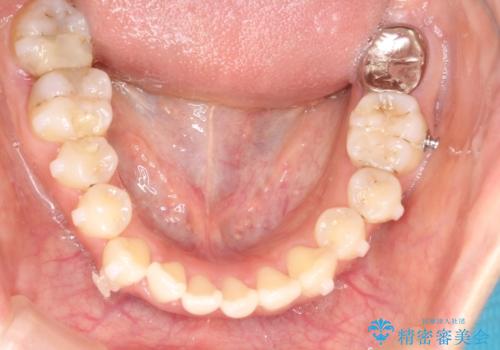

八重歯をインビザラインで非抜歯矯正

- 八重歯を主訴に来院されました。

インビザラインにて奥歯を後方に移動して八重歯が入るスペースを確保してく矯正する計画としました。

八重歯と前歯のガタガタがなくなり、歯並びがきれいになったのと、かみ合わせも改善することができました。